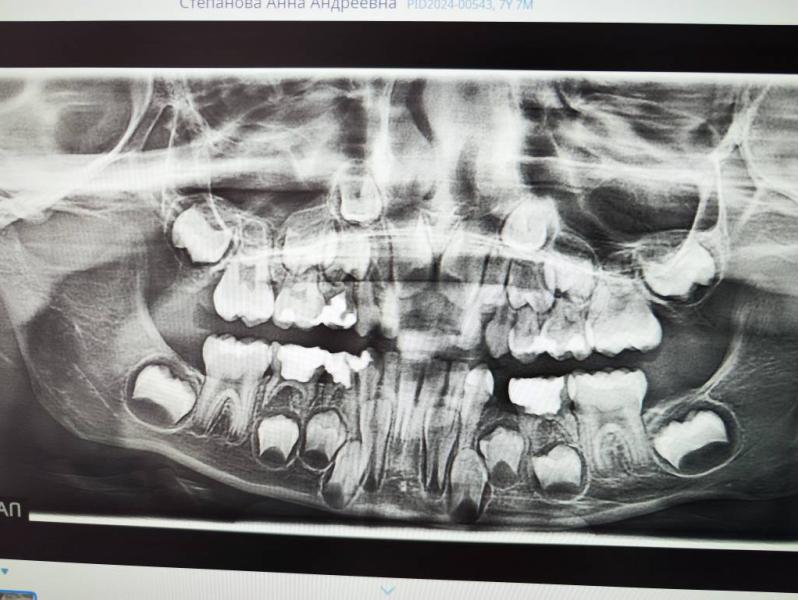

Жуткие снимки зубов у детей: как это выглядит?

Как страшно выглядят детские снимки зубов 😂😂😂

Ага, поэтому вот к ортодонту и пошли и снимок делали. Будем кольцо ставить.